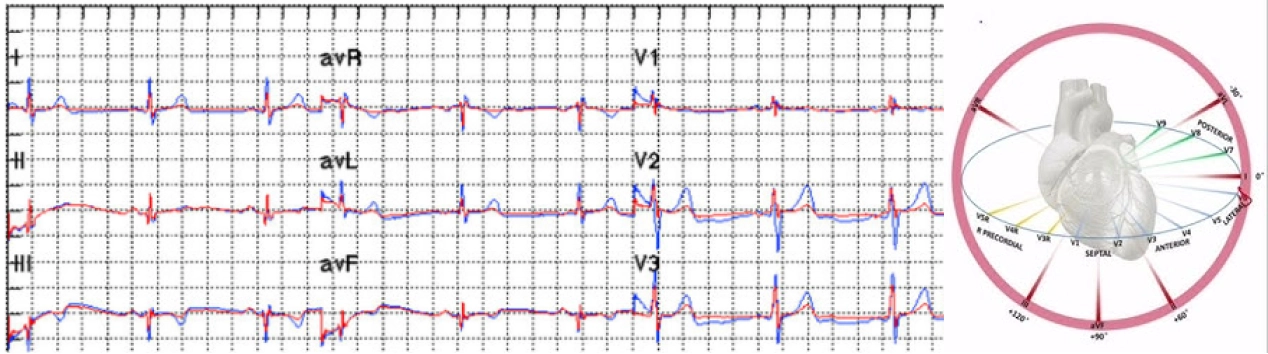

Powered by advanced AI and deep learning, it analyzes heart data in real time, detecting irregularities and early signs of conditions like coronary occlusion. With FDA-approved cardiac health models, the LUKE Virtual Doctor ensures precise and dependable monitoring to safeguard patient health.